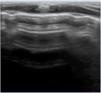

Neonatal respiratory distress syndromeRespiratory distress syndrome results from a primary (preterm neonates) or secondary (term neonates) deficiency of surfactant, and manifests with pulmonary oedema and decreased lung volume (collapse or atelectasis). It sonographic appearance is characterised by the loss of aeration with a homogeneous AI pattern and an irregular or thickened pleural line, resulting in a uniformly hyperechoic lung field (white lung),13 with condensations that may range from small subpleural collapses to large consolidations with air bronchogram (atelectasis), possibly associated with subclinical pleural effusion (Fig. 4, Video S10). Depending on the severity and course of disease, there may be different degrees of involvement in each field or hemithorax.1–3,19

Respiratory distress syndrome. A, B and C: preterm neonate born at 30+2 wk. Urgent caesarean section without prenatal steroids. Lung ultrasound at admission: (A) Anterior plane: homogeneous alveolar-interstitial pattern without areas of aeration (no A-lines) and irregular pleural line, white lung. (B) Lateral plane, similar findings. (C) Posterior plane: alveolar-interstitial pattern with pleural thickening and subpleural consolidations in lung base. (D) Transverse plane: alveolar-interstitial pattern with subpleural consolidations (arrow). (E) Posterior longitudinal plane with alveolar-interstitial pattern with pleural thickening, subpleural consolidations and consolidation with air bronchogram (atelectasis) in 2 intercostal spaces (arrow).